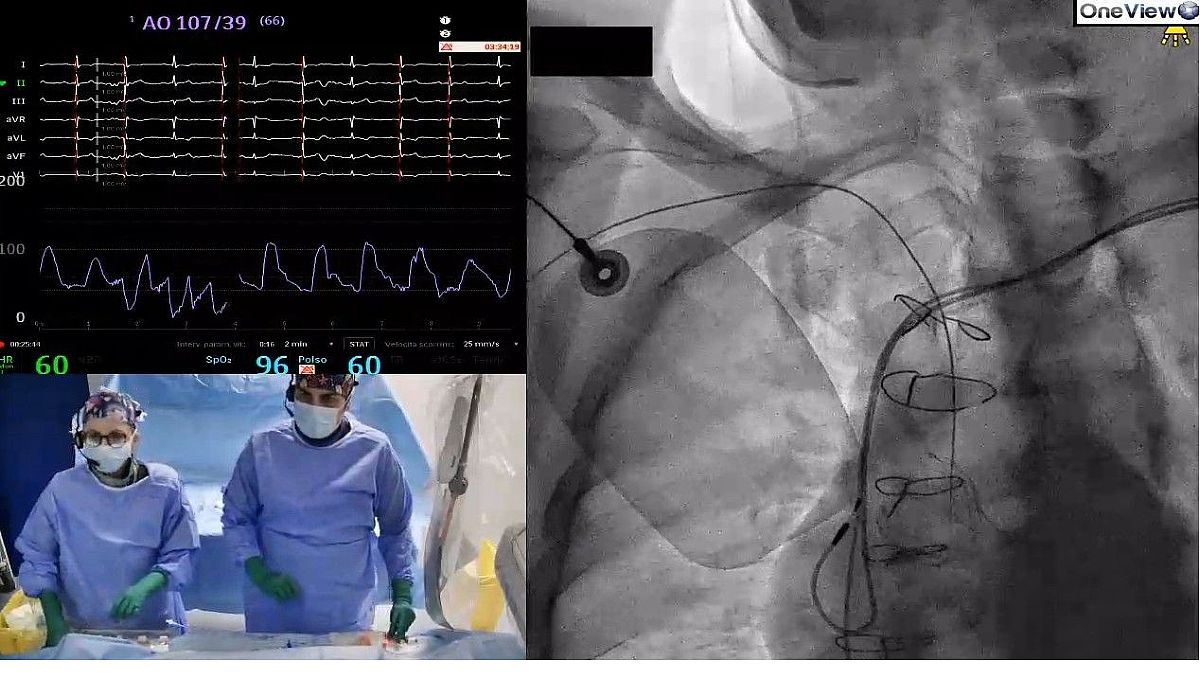

Tecnologia e procedure chirurgiche: al PO di Eboli eseguito un accesso radiale durante una denervazione renale registrato tramite il sistema OneView

Ulteriore innovazione è stata l’utilizzo durante l’intervento del sistema OneView, tecnologia che consente di registrare l’intera procedura e trasmetterla in diretta, permettendo così ad altro personale medico collegato da altri centri di assistere all’intervento in tempo reale, rendendo possibile uno scambio di informazioni e una collaborazione a distanza durante le procedure, oltre ad una formazione continua del personale.

Il sistema OneView è progettato per rivoluzionare l'educazione digitale non solo per la cardiologia interventistica, ma anche nell'ambito della radiologia e della chirurgia vascolare. Questo sistema consente di acquisire fino a otto dispositivi digitali (tra cui fluoroscopio, ultrasonografia intravascolare, tomografia a coerenza ottica, poligrafo, ecografo etc.) ed è costituito da: postazione di lavoro, due telecamere di sala, auricolari per il personale medico.